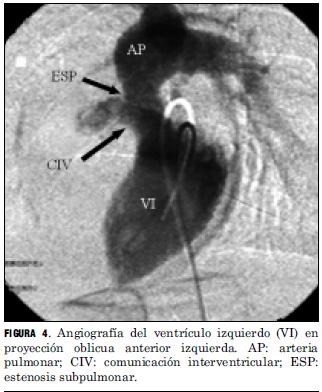

El análisis anatómico destaca que 40 pacientes presentaron D-TGA con séptum interventricular intacto y 20 con comunicación interventricular. Uno de estos pacientes asoció una coartación de aorta con severa hipoplasia del arco aórtico, otro era portador de un situs inversus (figuras 2 y 3), y otro presentaba una estenosis subpulmonar leve (tabla 4, figura 4).

Las lesiones residuales significativas se presentaron en nueve pacientes (15%). Siete pacientes con estenosis supravalvular pulmonar, uno de ellos asociada a estenosis del origen de la arteria pulmonar rama izquierda, que requirieron angioplastia con balón (figuras 6 y 7), siendo efectiva en cuatro, mientras que en los otros tres requirió cirugía reparadora con la colocación de parche de pericardio bovino. Un paciente presentó una comunicación interauricular residual que debió ser cerrada quirúrgicamente, y otro paciente desarrolló una estenosis subaórtica (figura 8) que se resecó quirúrgicamente, todos con buena evolución (tabla 5).

La frecuencia de aparición de lesiones residuales significativas en nuestra serie fue similar a la publicada en la literatura, donde se refiere para la estenosis supravalvular pulmonar una incidencia de 5% a 30%, siendo menor su incidencia con el aumento de la experiencia del equipo. Son factores favorecedores de su aparición la corrección neonatal precoz, la existencia de un banding con larga evolución, la hipoplasia del anillo aórtico y la técnica quirúrgica empleada (16). En los casos de estenosis supravalvular pulmonar hemos tenido un porcentaje de éxito mediante la valvuloplastia con catéter balón, superior al promedio registrado en la literatura. Creemos que ello pueda deberse a múltiples variables a saber: técnica quirúrgica empleada, tamaño de muestra insuficiente para obtener conclusiones estadísticamente significativas. La aparición de una estenosis subaórtica significativa correspondió a un paciente que presentó una leve estenosis subpulmonar previo a la realización del switch arterial, subvalorada en el momento de la realización de dicha técnica.